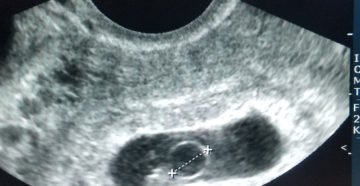

Плодное яйцо Если врач во время ультразвукового исследования сообщает, что видит в полости матки плодное…